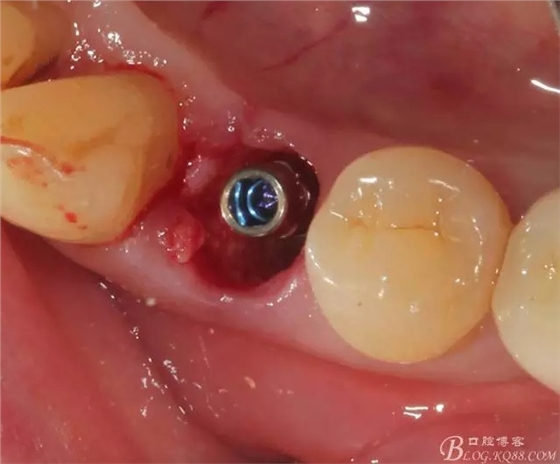

簡(jiǎn)單備洞以后植入種植體 植體和頰側(cè)空間距離大于2毫米 注意沒(méi)有植骨

這個(gè)角度更能看到植體與頰側(cè)骨壁的空間了

適當(dāng)塞入膠原塞 簡(jiǎn)單縫合